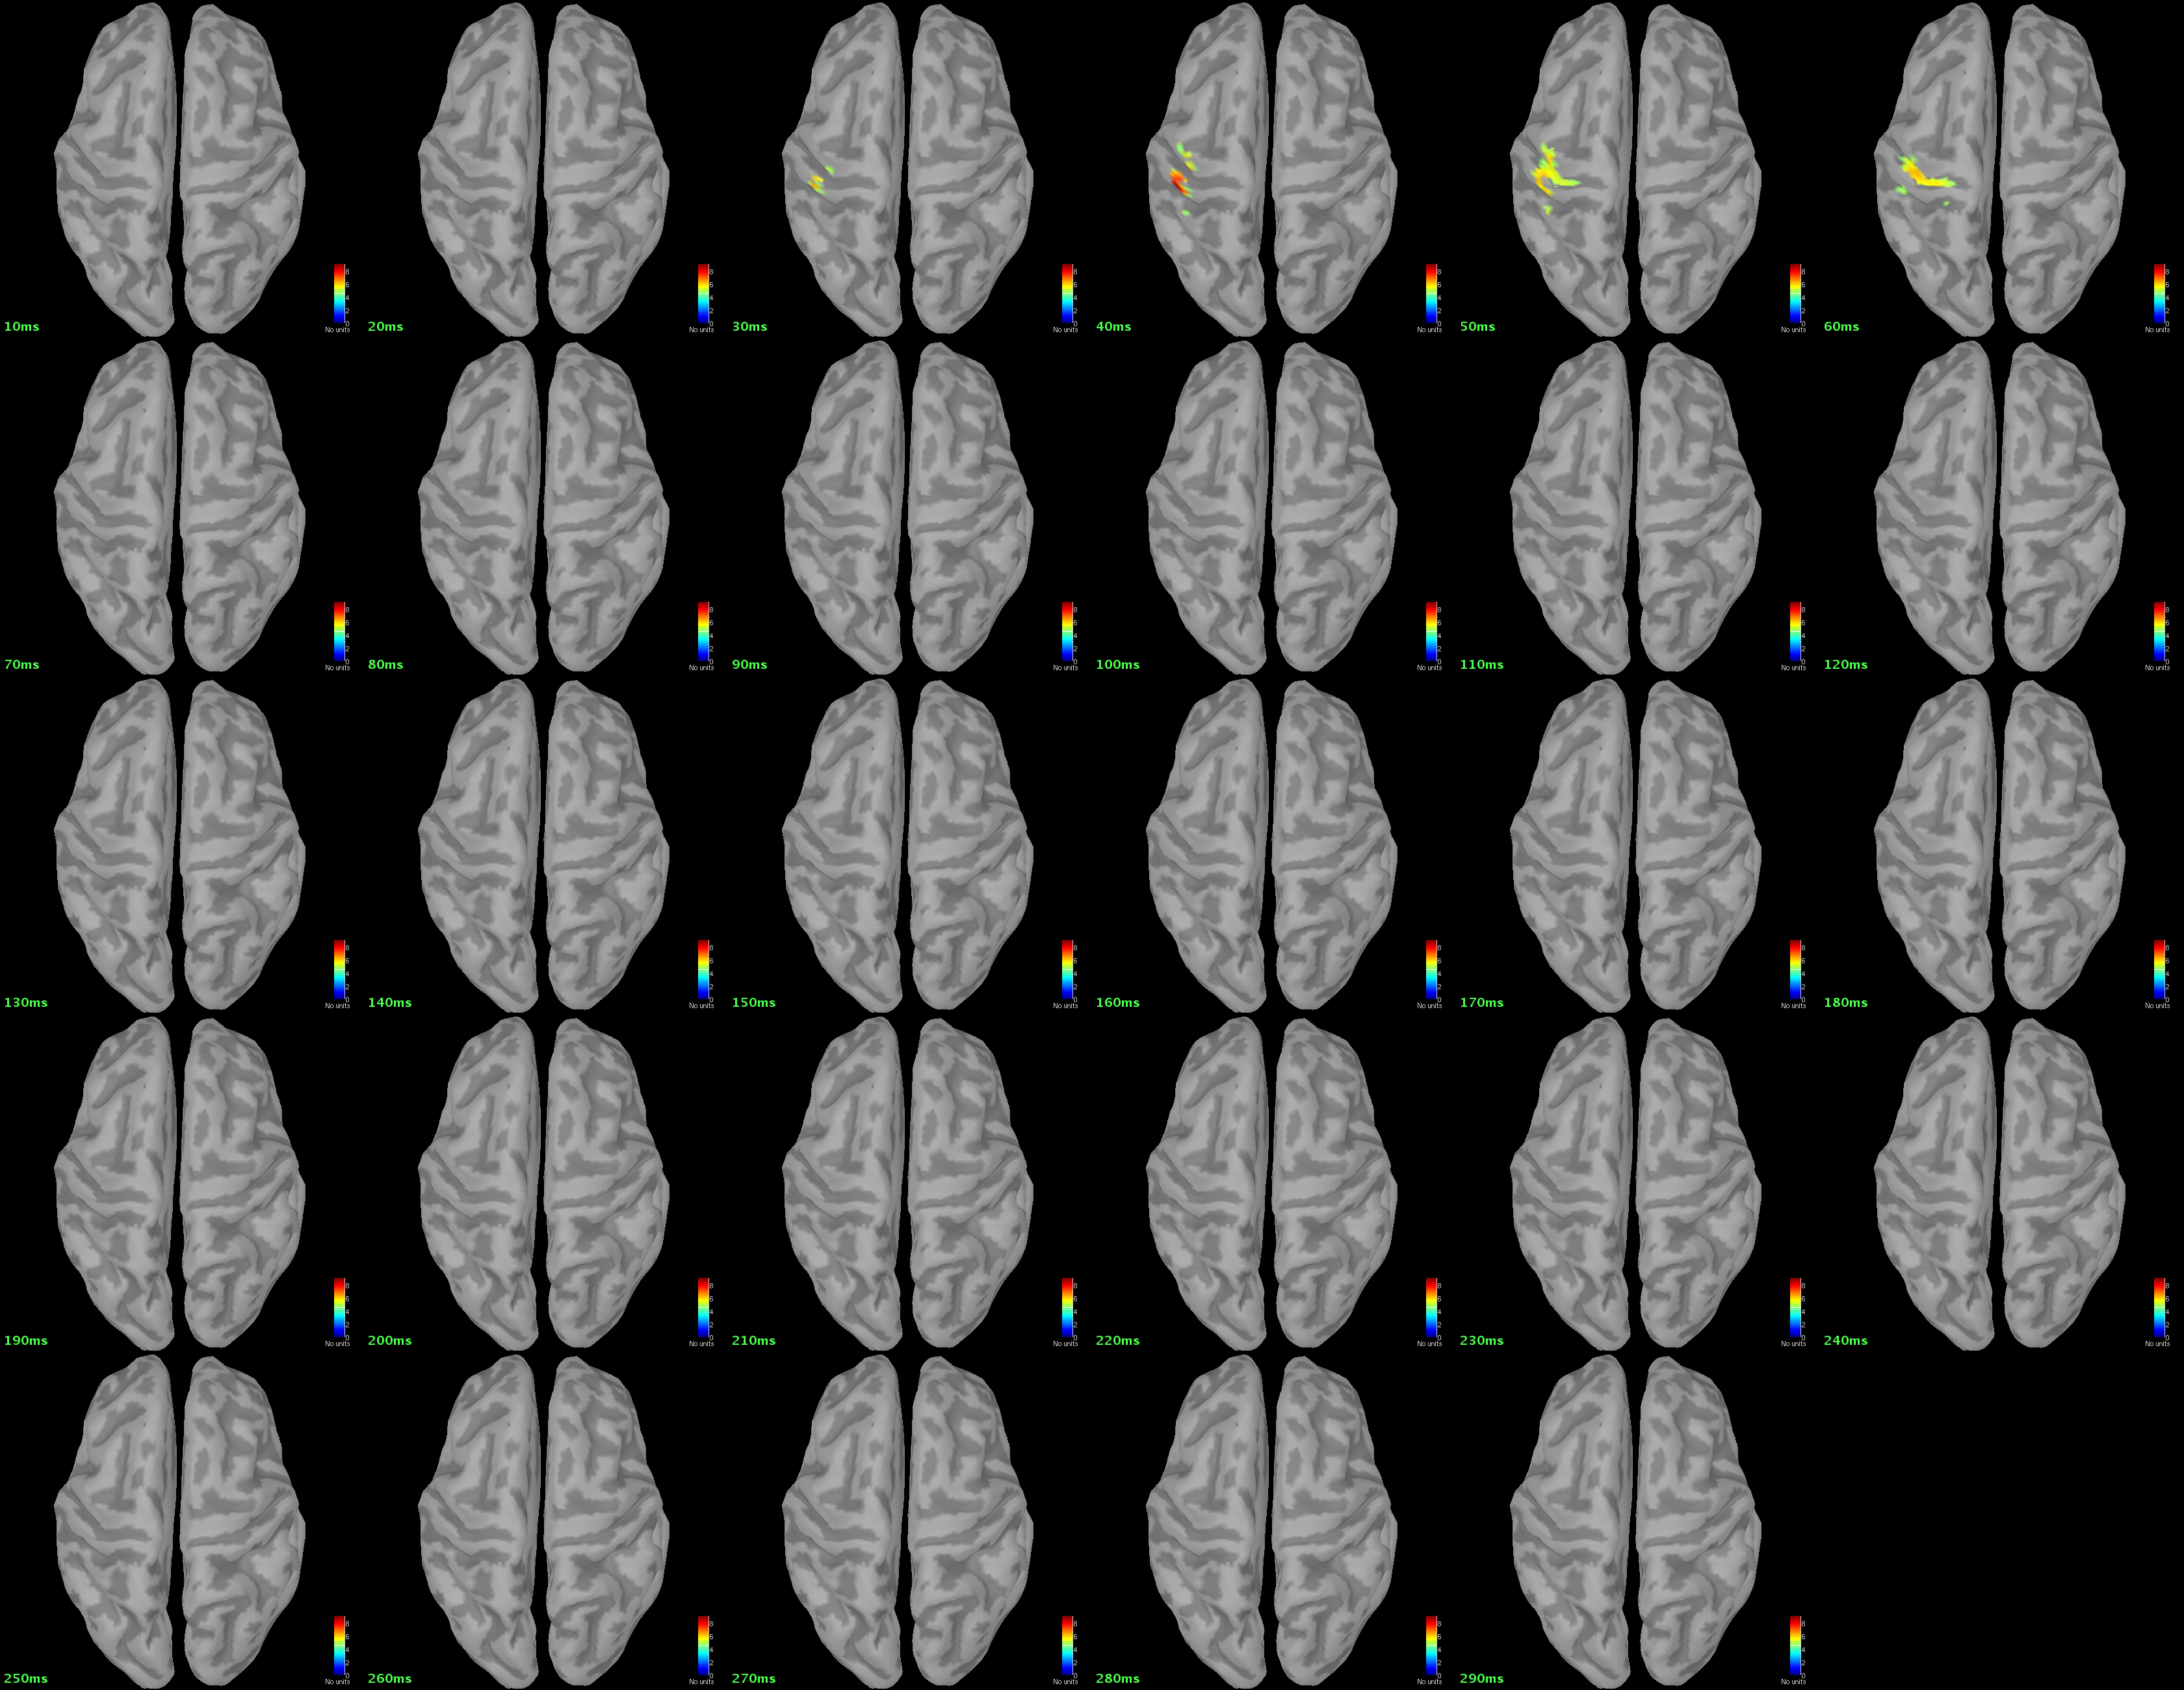

Attachment 'NAIrightmap.png'